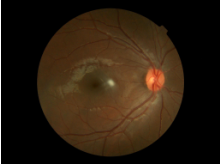

眼科常规检查:远视力:右裸眼1.0,左裸眼 1.0。双眼位正,眼球各方向运动到位。双眼结膜无充血,角膜清,前房中深,KP(-),Tyn(-)。双眼瞳孔基本等大正圆,对光反应(++);双眼晶体清,双眼玻璃体轻度泥沙样混浊。小瞳下眼底:双眼视神经乳头色正界清,血管走行正常,黄斑部中心凹光反射(±)。(眼底像见附件1)

附件1:眼底像

右眼底

左眼底